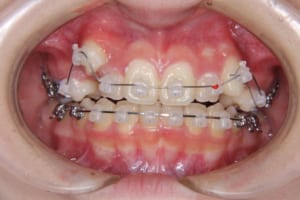

治療中